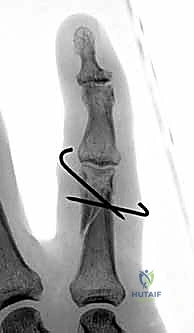

- كسور السلامية القريبة (Proximal Phalanx Fractures): غالباً ما تتخذ هذه الكسور زاوية راحية (Apex Volar Angulation). يحدث هذا لأن العضلات بين العظام (Interosseous muscles) تسحب الجزء القريب من الكسر نحو الثني، بينما تسحب آلية الباسطة الجزء البعيد نحو المد.

- كسور السلامية الوسطى (Middle Phalanx Fractures): يعتمد اتجاه الانزياح هنا على موقع الكسر بالنسبة لمكان التصاق الوتر القابض السطحي (FDS). إذا كان الكسر قريباً من الالتصاق، فإن الجزء البعيد ينثني. وإذا كان الكسر بعيداً عن الالتصاق، فإن الجزء القريب ينثني.

- تشوه مرئي في الإصبع: قد يبدو الإصبع أقصر من الطبيعي، أو منحنياً بزاوية غير طبيعية، أو ملتفاً حول محوره (Malrotation).

- ظاهرة تداخل الأصابع (Scissoring): وهي من أهم العلامات السريرية التي يبحث عنها د. هطيف. عند محاولة المريض إغلاق يده (صنع قبضة)، يتقاطع الإصبع المكسور فوق أو تحت الإصبع المجاور بدلاً من أن يشير بشكل متوازي نحو العظم الزورقي في المعصم. هذا يدل على وجود تشوه دوراني يجب تصحيحه جراحياً.